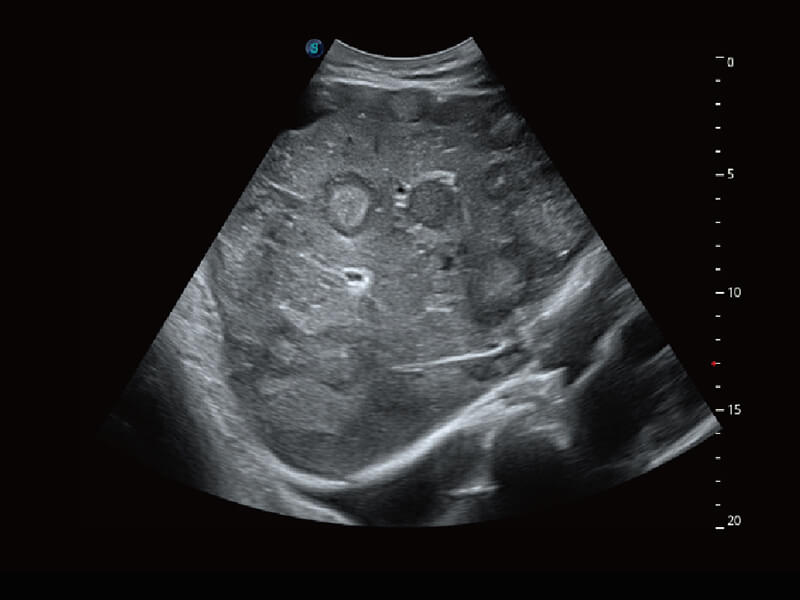

性能优异的硬件架构,极大提升超声系统的运行效率和数据处理能力。相比以往超声成像系统,Wis+平台为您带来极快的响应速度和成像帧频,提升检查流畅度。